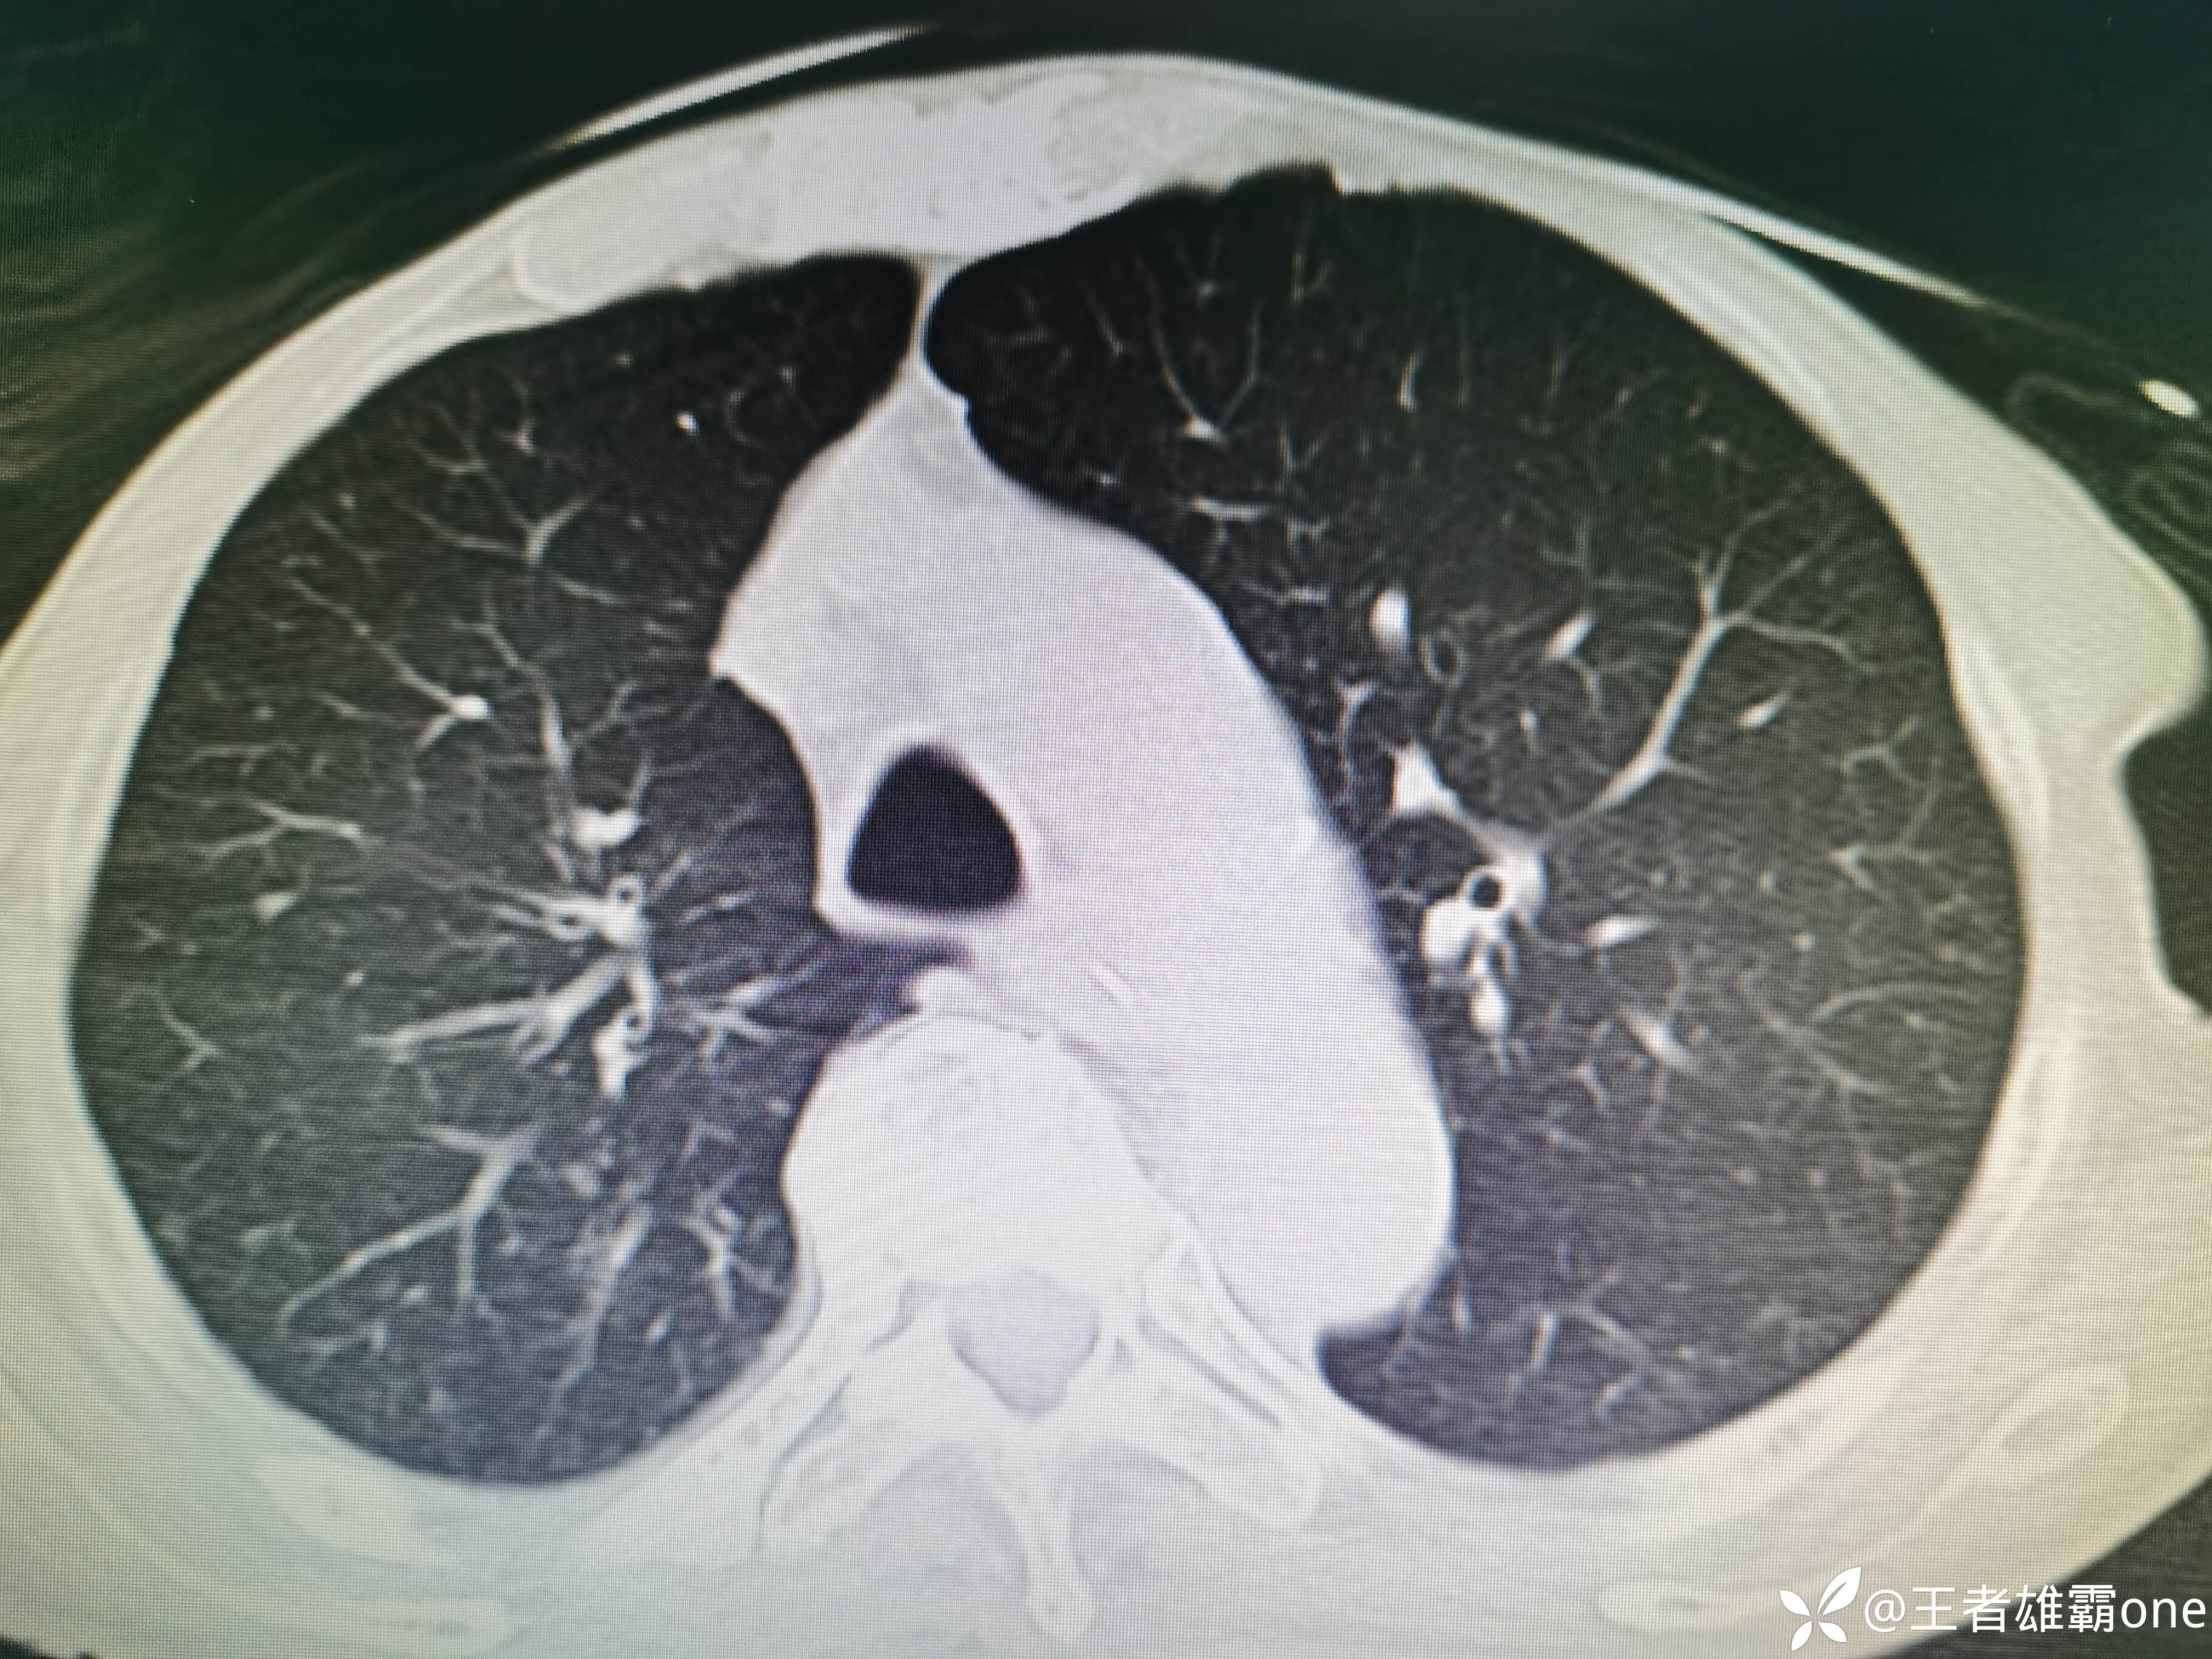

入院时胸部CT:

具体图片: